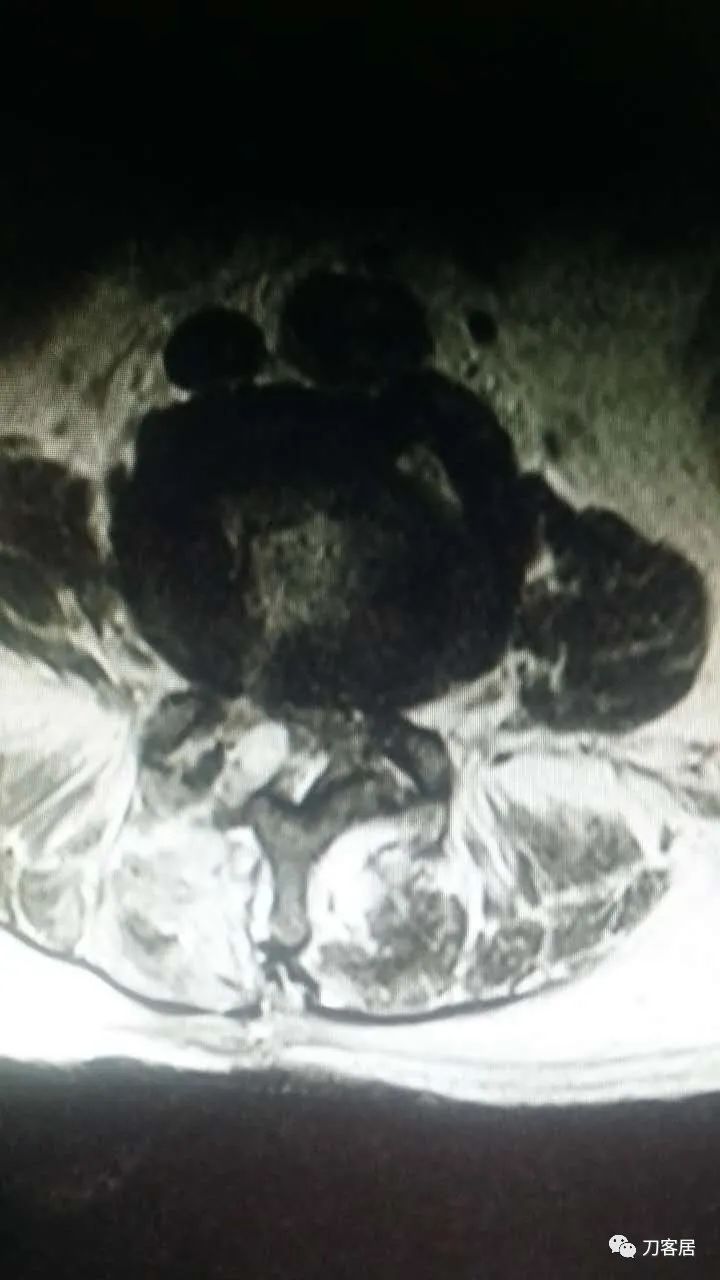

加注图10: 腰1-2椎管内后方可见梭形占位信号改变。

加注图11. 腰1-2椎管内后方可见梭形占位信号改变。

好像是,上面有血肿。